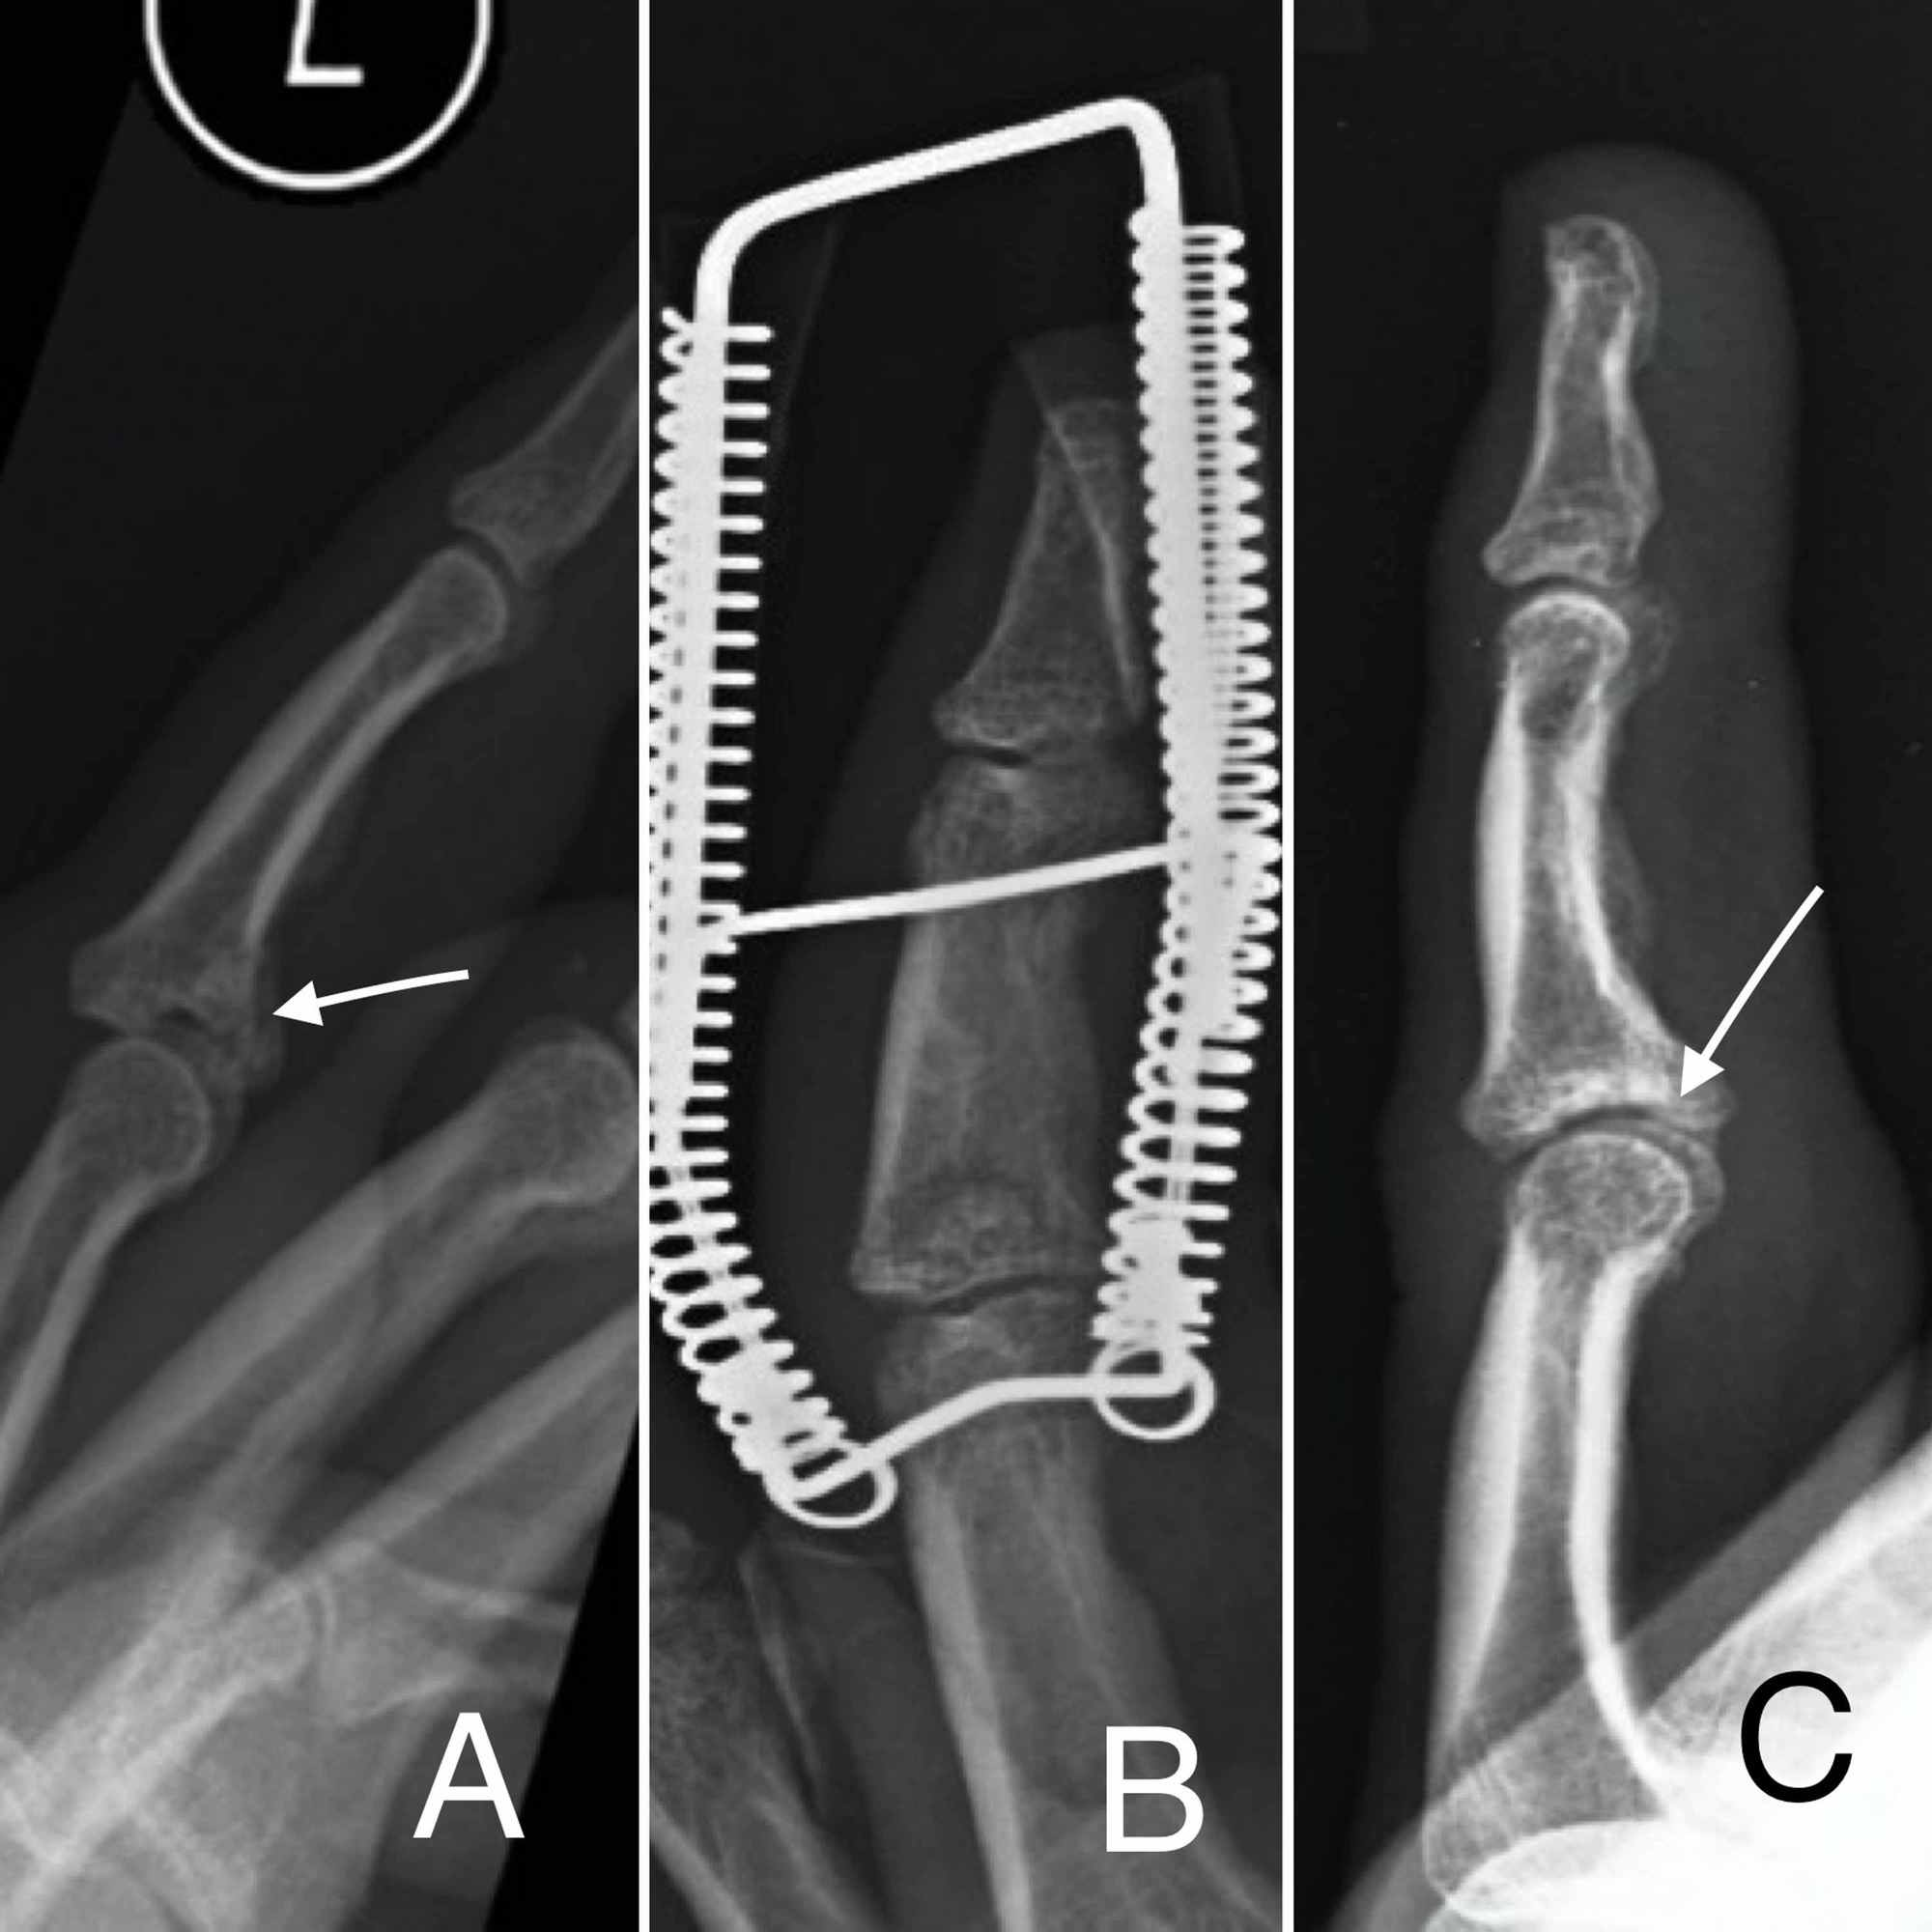

From www.semanticscholar.org

Figure 1 from Extension Block Pinning for Unstable Proximal Interphalangeal Joint Dorsal Unstable Dip Joint injuries to the distal interphalangeal (dip) joint, which range from mild sprains to complete ligament ruptures and joint. This blog discusses how to identify and treat. Of all the joints in the. unstable dip joint dislocations require prolonged extension block splinting with continuous monitoring by hand therapy for splint adjustment, etc. the distal interphalangeal (dip) joint is. Unstable Dip Joint.

From www.researchgate.net

A patient with unstable index finger proximal interphalangeal joint... Download Scientific Diagram Unstable Dip Joint this joint is called the distal interphalangeal (dip) joint in the fingers and the interphalangeal (ip) joint in the thumb. This blog discusses how to identify and treat. injuries to the distal interphalangeal (dip) joint, which range from mild sprains to complete ligament ruptures and joint. common traumatic injury of the hand involving the proximal interphalangeal joint. Unstable Dip Joint.